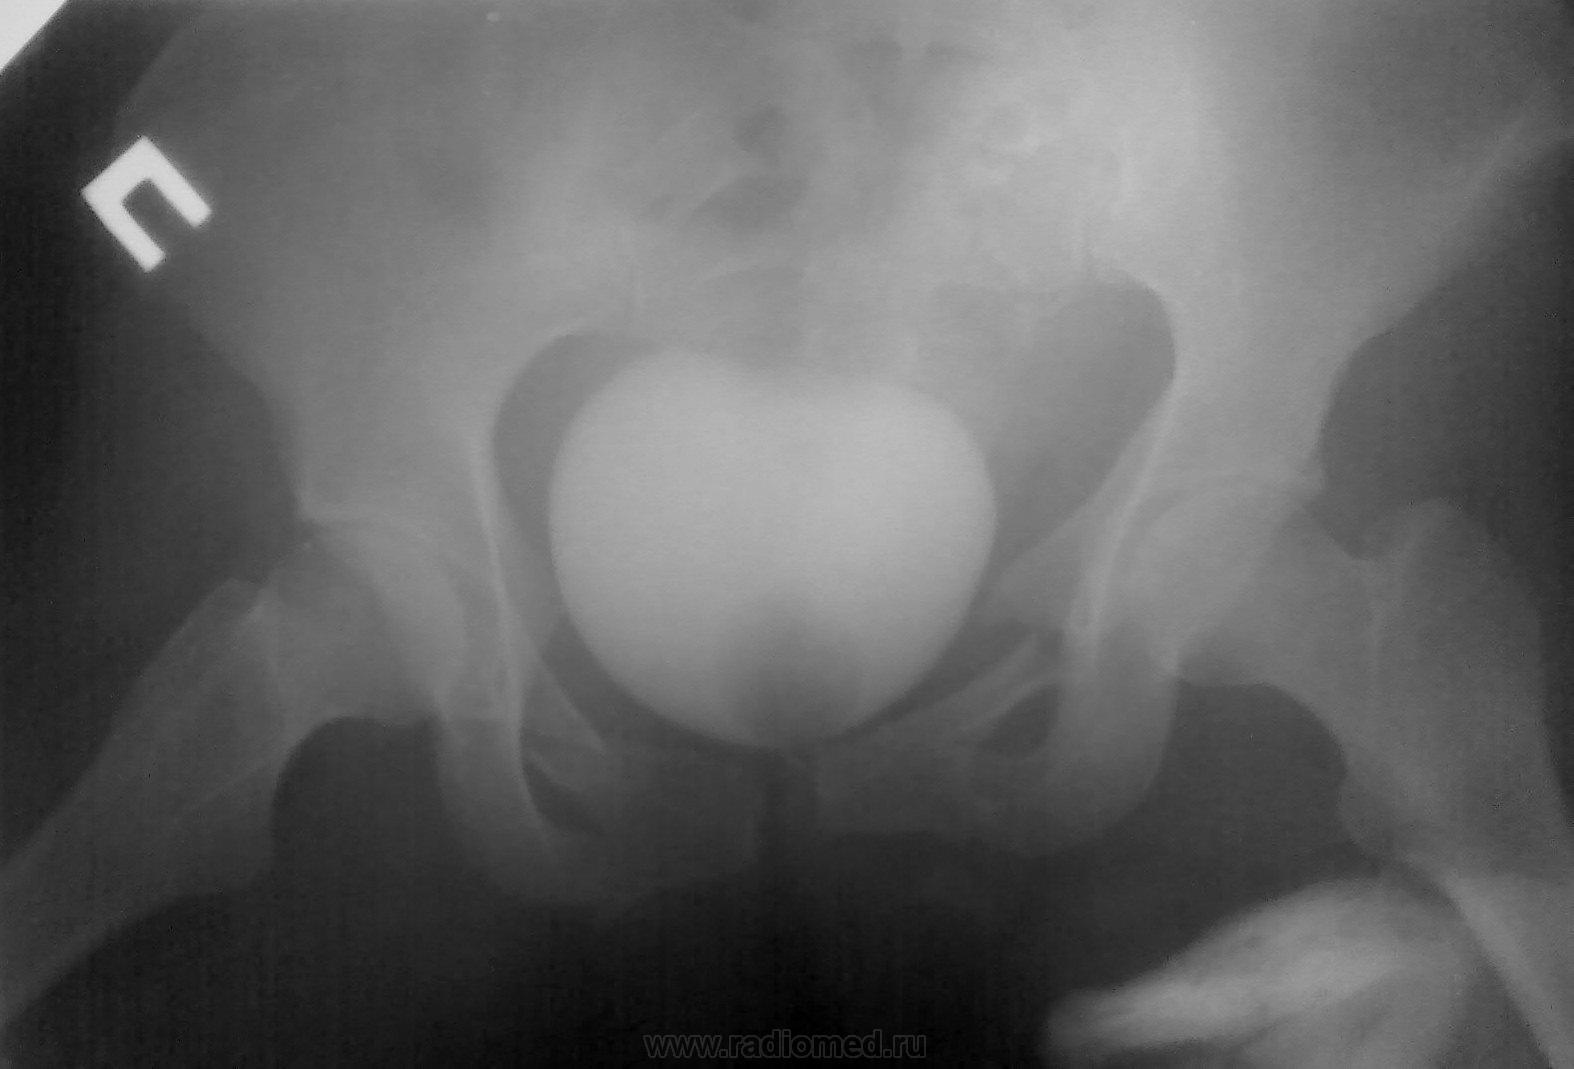

Мужчина. ДТП, этим все сказано....ну и - всего много...

2. Оскольчатая бабочка + разрыв симфиза. С левой подвздошной в крыле - не совсем уверена. Удивительно, что мочевой цел... или ошибаюсь?

2. И крыло подвздошной, и левая половина крестца, и поперечный пятого поясничного - все так и есть... Да, на удивление, мочевой "удержал")))

А по крестцу - каша, не понять... Поперечный 4-го отлетел слева, а в поперечном 5-м видится асимметричная сакрализация. Крыло погнуто наверняка, но деталей не могу рассмотреть, наощупь всё). Мочевой - молодец, железный мочевой)).

А во втором случае - таз всмятку!

Случай №2. Перелом крестцовоподвздошного сочленения слева со смещением подвздошной кости. Двусторонний перелом лонных и седалищных костей, разрыв лонного сочленения.

2. Повезло при такой -то травме. Во "скоко" оценили кровопотерю?